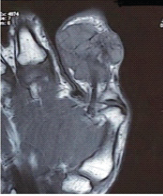

Microscopy showed a well-circumscribed dermal and subcutaneous tumor composed of uniform round cells with eosinophilic cytoplasm and centrally located round nuclei, arranged in nests and trabeculae. The tumor was richly vascular, consistent with a diagnosis of glomangioma, a variant of glomus tumor (Fig. 4). There was no evidence of malignancy or atypia.

Figure 4: Microscopy examination findings of excised mass (low power ×20 magnification).